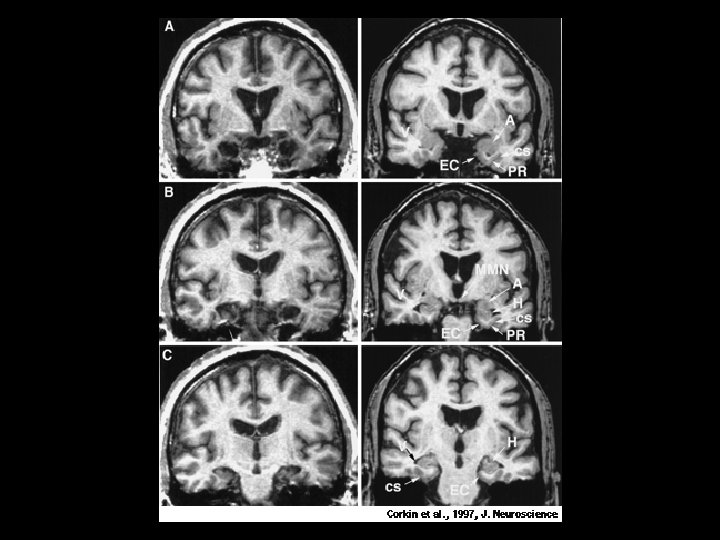

The Case of Henry M (H. M. )